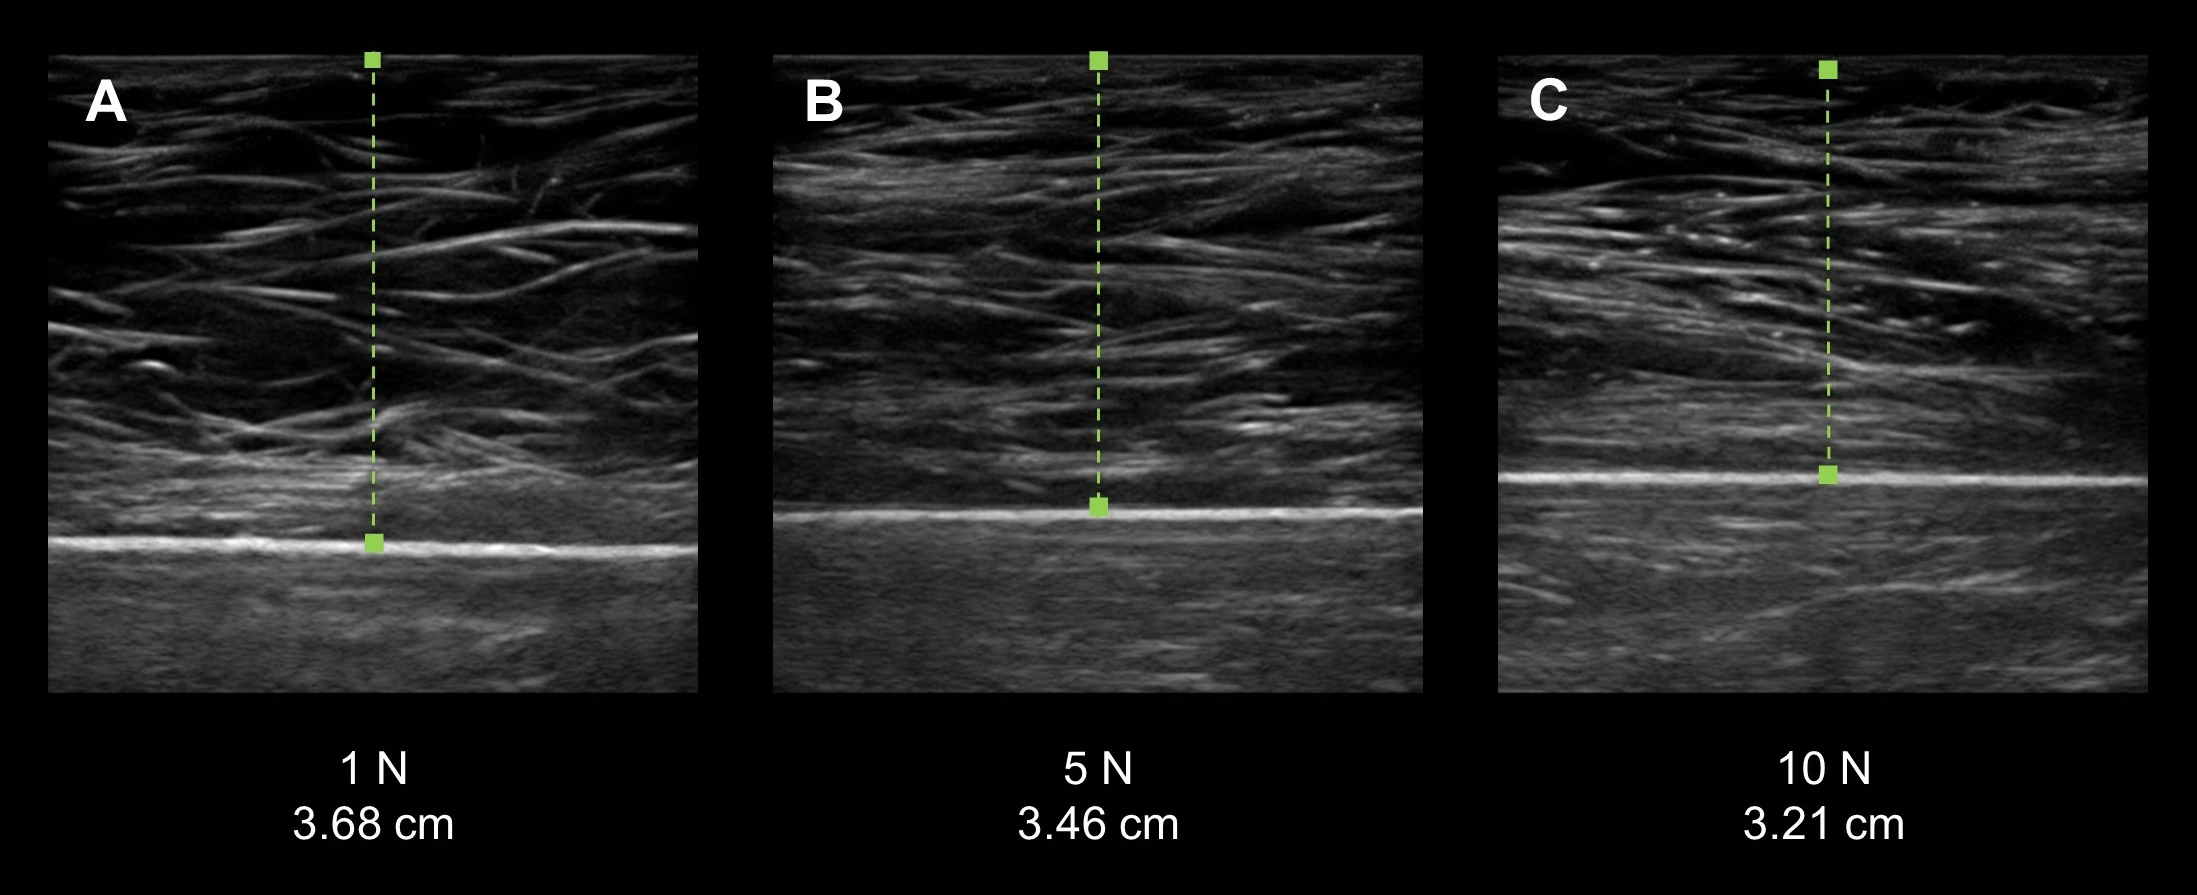

From peerj.com

Interrater reliability of quantitative ultrasound using force feedback Internal Ultrasound Cramping Can internal ultrasound cause cramping? Having an internal ultrasound is a lot more intrusive than an abdominal one and can cause some side effects especially if you are pregnant. I've had this scan twice before and it was uncomortable. From the moment the sonographer used the internal probe i had the worst cramping/stabbing pain ever and started crying. Transvaginal ultrasounds. Internal Ultrasound Cramping.